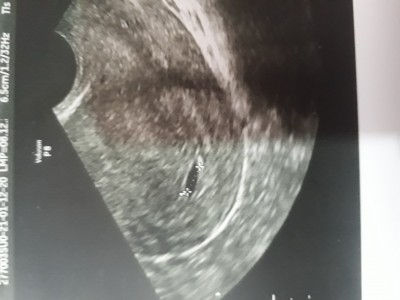

image

bende şöyle bir kese göründü buna dış gebelik olabilir dedi çok korkuyorum

(11 puan)

Neye dayanarak dış gebelik dedi doktorunuz? Ben de 5 haftalıkken gittim sadece kese vardı. Ondan sonra 4 hafta filan sonra tekrar gittim bebek göründü ve kalp atışı aldık çok şükür. Bu süre içerisinde beslenmeme çok dikkat ettim ve kalsiyum protein ne varsa ağırlıklı yemiştim. Doktorlara da güven olmuyor çünkü hemen kürtaj ya da dış gebelik diyorlar çok etkileniyoruz. Sen bekle bı muddet daha zaten dış gebelik belirtileri varsa kendinde ki inşallah olmaz bilirsin.